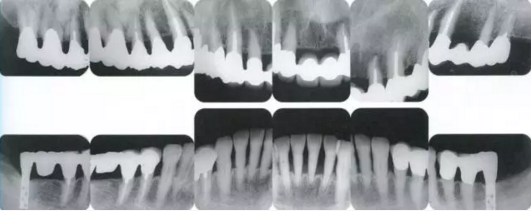

22222222222222.png

▲圖19-2,3

上下頜咬合面照。

22222222222222222222222222.png

▲圖19-4

X光片。牙槽骨明顯缺失。